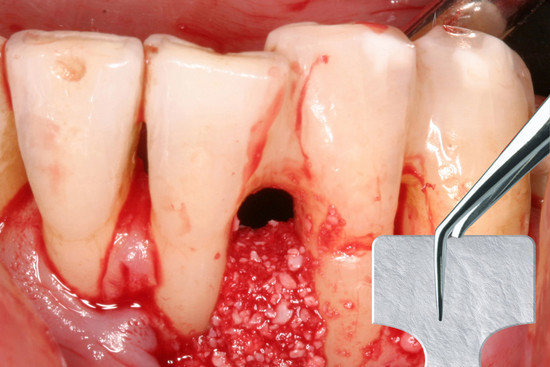

- Przytnij membranę do pożądanego kształtu za pomocą przygotowanego szablonu zachowując 3 mm margines w stosunku do ubytku.

- Nałóż suchą membranę szorstką stroną skierowaną w stronę ubytku.

Dostosowanie do rozmiaru ubytku.

Stosować na sucho – zwilżyć w miejscu aplikacji (dzięki uprzejmości prof. Christgau, Dusseldorf, Niemcy).